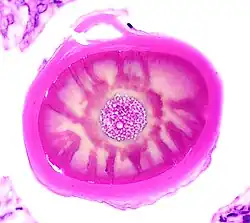

Histology of a multilayered corpus amylaceous of the prostate.

The composition and appearance of corpora amylacea can differ in different organs.[3] In the prostate gland, where they are also known as prostatic concretions, corpora amylacea are rich in aggregated protein that has many of the features of amyloid, whereas those in the central nervous system are generally smaller and do not contain amyloid.[3] Corpora amylacea in the central nervous system occur in the foot processes of astrocytes, and they are usually present beneath the pia mater, in the tissues surrounding the ventricles, and around blood vessels.[2] They have been proposed to be part of a family of polyglucosan diseases, in which polymers of glucose collect to form abnormal structures known as polyglucosan bodies.[3] Polyglucosan bodies bearing at least partial resemblance to human corpora amylacea have been observed in various nonhuman species.[3]